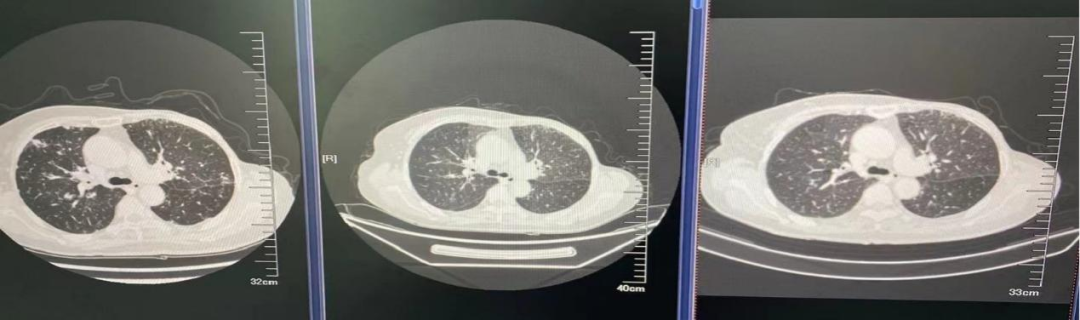

图4.肺窗

2021年4月7日双肺示:转移可能。